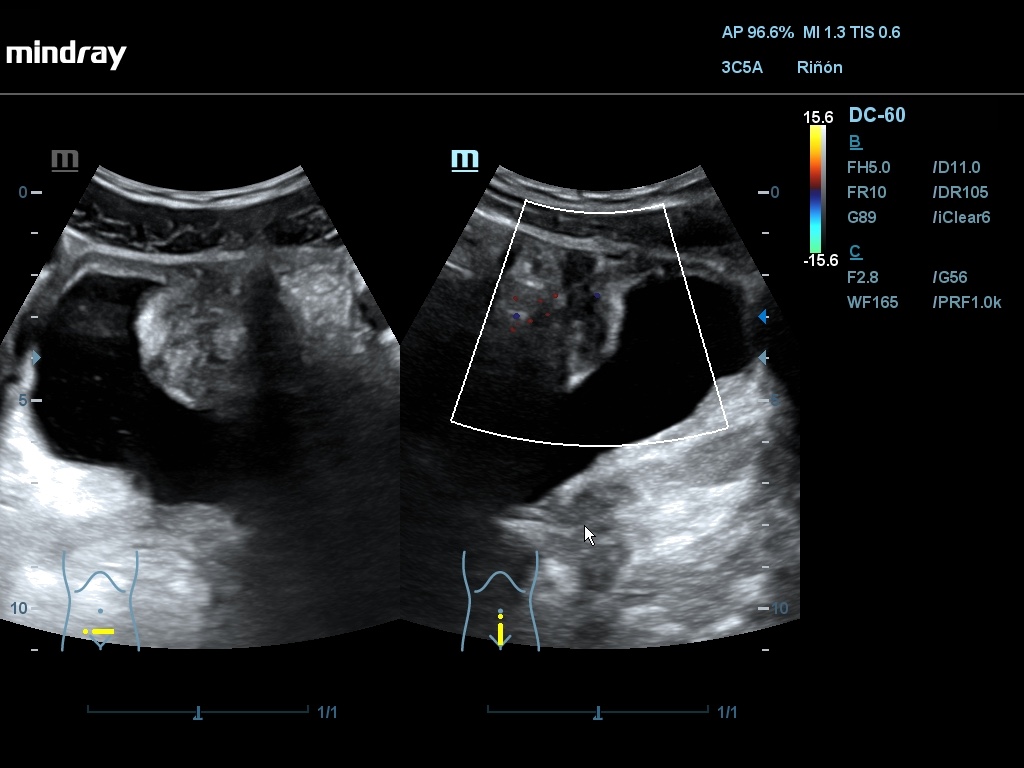

Ecografía: Se han observado varias imágenes poco habituales en vejiga urinaria: imágenes hiperecogénicas flotantes sin sombra posterior, móviles (detritus), engrosamiento de pared vesical que simula una vejiga no distendida con áreas anecoicas, pared con imagen en doble carril, masa vesical.

La sospecha inicial por criterios epidemiológicos es esquistosomiasis con afectación de vejiga urinaria. El diagnóstico diferencial se debe hacer con otras infecciones y tumores (raros en esta edad). En uno de los casos, AE considera que las imágenes se deben a vejiga poco replecionada y no las valora como patológicas. La masa vesical podría ser de tipo inflamatorio o tumoral.